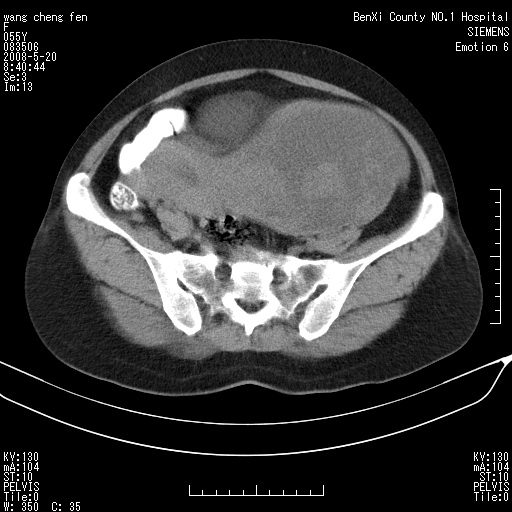

女、绝经后阴道流血3个月

左侧附件区可见一囊性占位,边缘清楚,内可见不规则形软组织影 ce:囊壁及内部可见强化 考虑 卵巢囊腺瘤

左侧附件区巨大囊实性病灶,边缘光整,病灶囊壁较厚,增强示囊壁及实性部分明显强化,强化呈度与宫体实质大致相同,宫腔积液征像,未见盆腔积液等其他异常,考虑左侧卵巢囊腺癌,不除外囊腺瘤及浆膜下肌瘤坏死

左侧附件区巨大囊实性病灶,边缘光整,病灶囊壁较厚,增强示囊壁及实性部分明显强化,强化呈度与宫体实质大致相同,宫腔积液征像,未见盆腔积液等其他异常。绝经后阴道流血3个月,结合病史左侧卵巢囊腺癌首先考虑,宫腔扩大不除外累及。期待结果。

支持浆膜下子宫肌瘤.之前由于网络原因未看全图片,现在重看,宫颈见一类圆形低密度影,增强轻度强化,低于肌层强化,宫腔扩大,考虑宫颈癌伴宫腔积液可能性大.

囊实性肿块分隔厚度较大,厚薄不均,增强实性成分明显强化,有不规则阴道流血,卵巢囊腺癌可能性大。

1,宫颈部占位,宫颈癌?2,左侧附件区囊实性占位,界较清,实质部分强化明显。考虑浆膜下或阔韧带肌瘤囊变可能大。囊腺类肿瘤不除外。